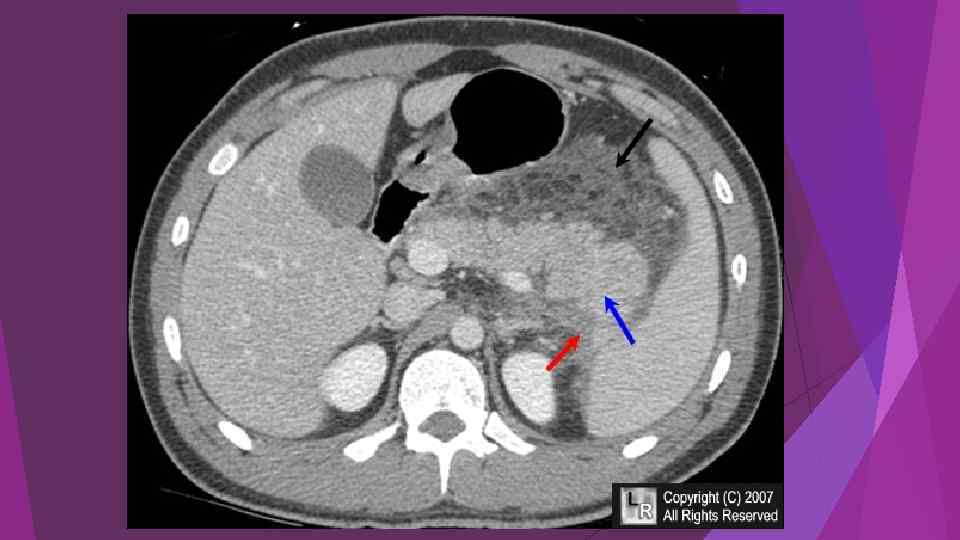

Острый панкреатит, деструктивная форма. Увеличение размеров

Острый панкреатит, деструктивная форма. Увеличение размеров

Diagnosis and differential diagnosis of acute pancreatitis are as follows: Accordi ng to the typical clinical manifestations and laboratory tests, can often make the diagnosis. Patients with mild persistent and severe abdominal pain, nausea, vomiting,

Diagnosis and differential diagnosis of acute pancreatitis are as follows: Accordi ng to the typical clinical manifestations and laboratory tests, can often make the diagnosis. Patients with mild persistent and severe abdominal pain, nausea, vomiting,